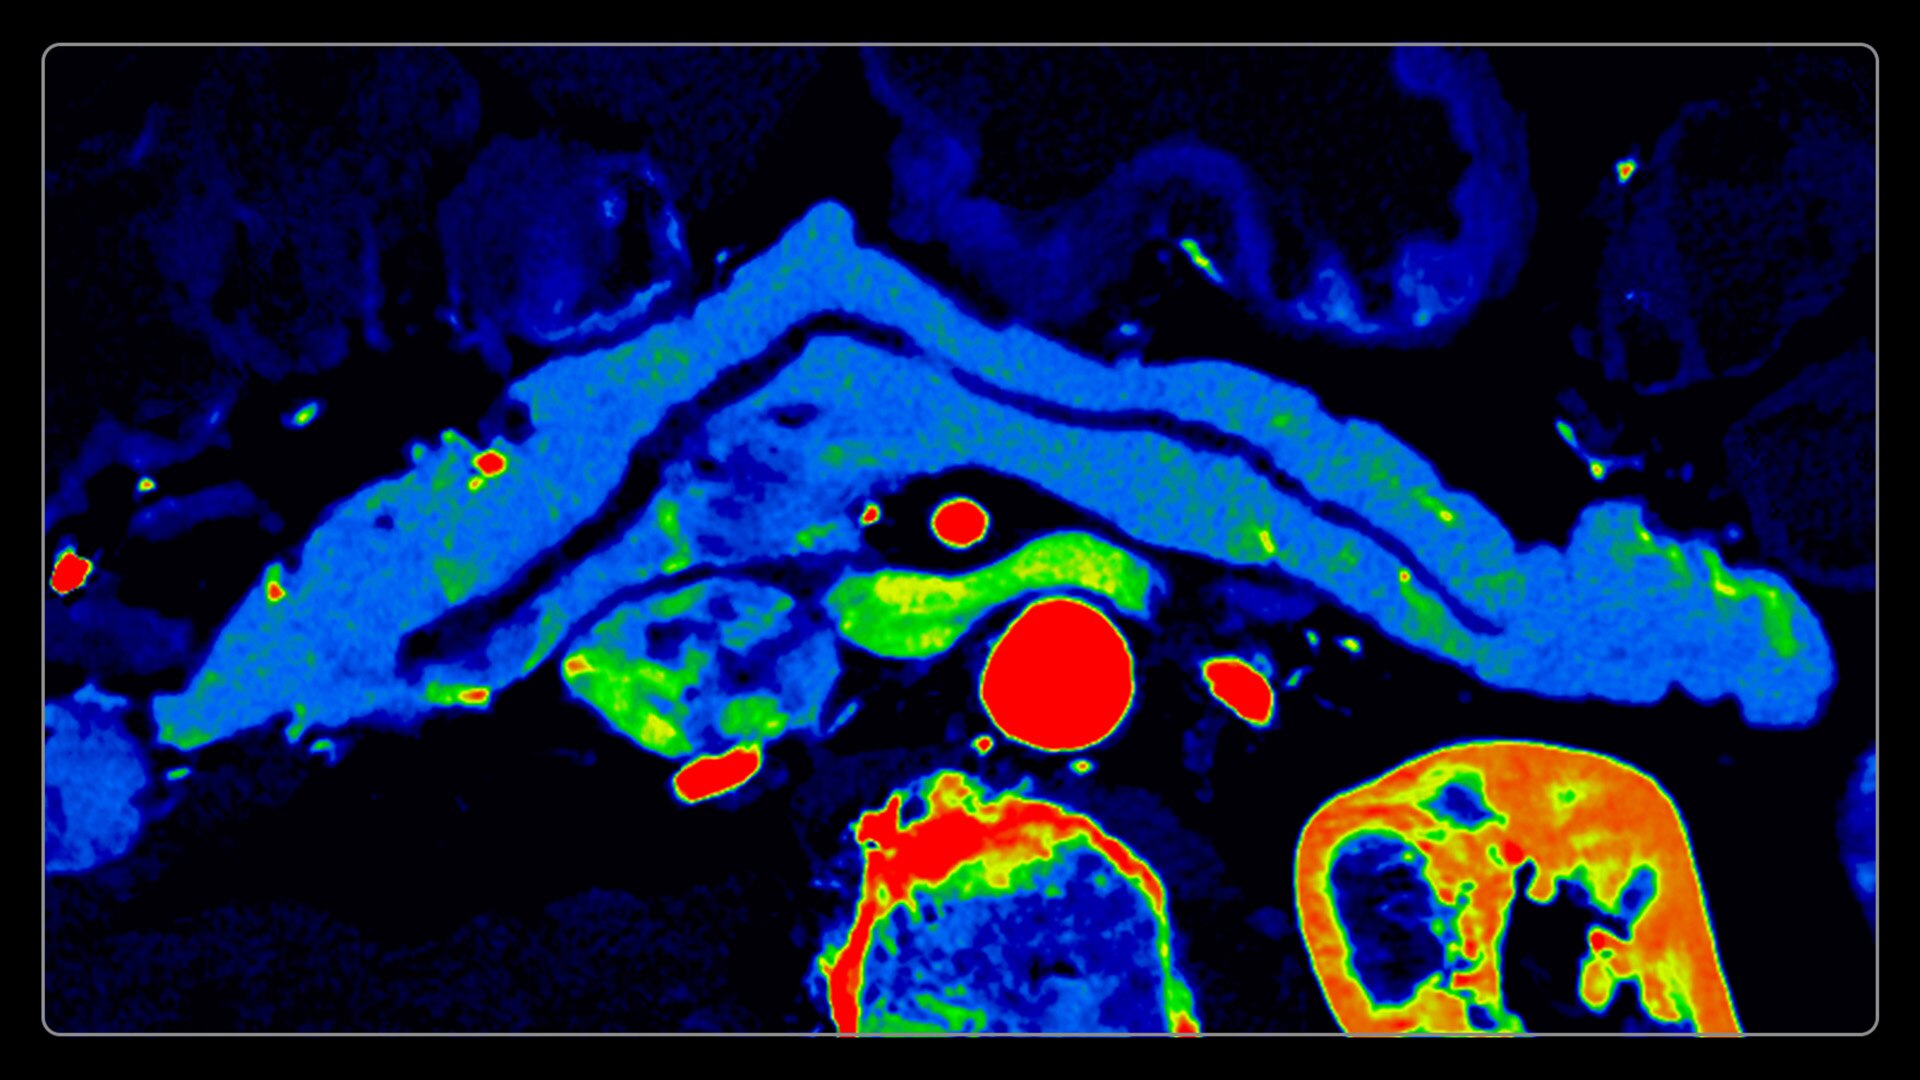

On-demand spectral imaging enabled by 8-energy bins

Our advanced spectral imaging capabilities are intended to allow you to experience the difference between seeing and knowing so you can confidently detect, characterize and monitor disease.

Photonova Spectra is also designed to enhance material separation for tissue characterization and disease quantification, bringing potentially greater diagnostic confidence in every acquisition across care areas.

A full range of spectral imaging series is generated natively on console and available for transfer to PACS. The full-fidelity spectral data acquisition is intended to provide native DICOM images and material maps to support clinical diagnosis, with improvements of up to 4x enhanced energy discretization1, 2x higher material map spatial resolution2, and 2x improved iodine detectability3.